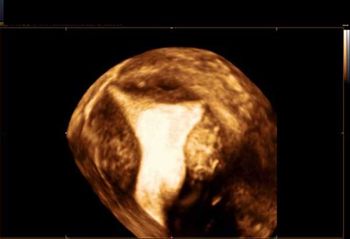

What is your diagnosis based on these images?